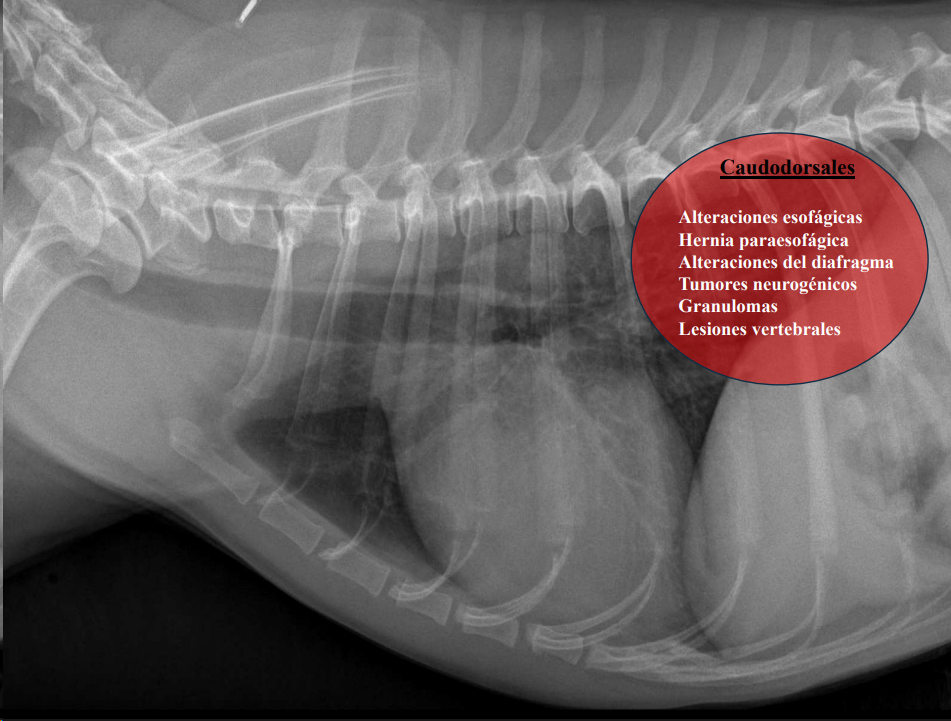

- Masas mediastínicas (craneodorsales, hilares, caudodorsales, caudoventrales, craneoventrales).

Caudodorsales: hernia paraesofágica, tumores neurogénicos, granulomas.

Craneodorsales: alteraciones esofágicas, aneurisma aórtico, hematoma, tumor base cardíaca/neurogénico, absceso, granuloma, lesión vertebral.